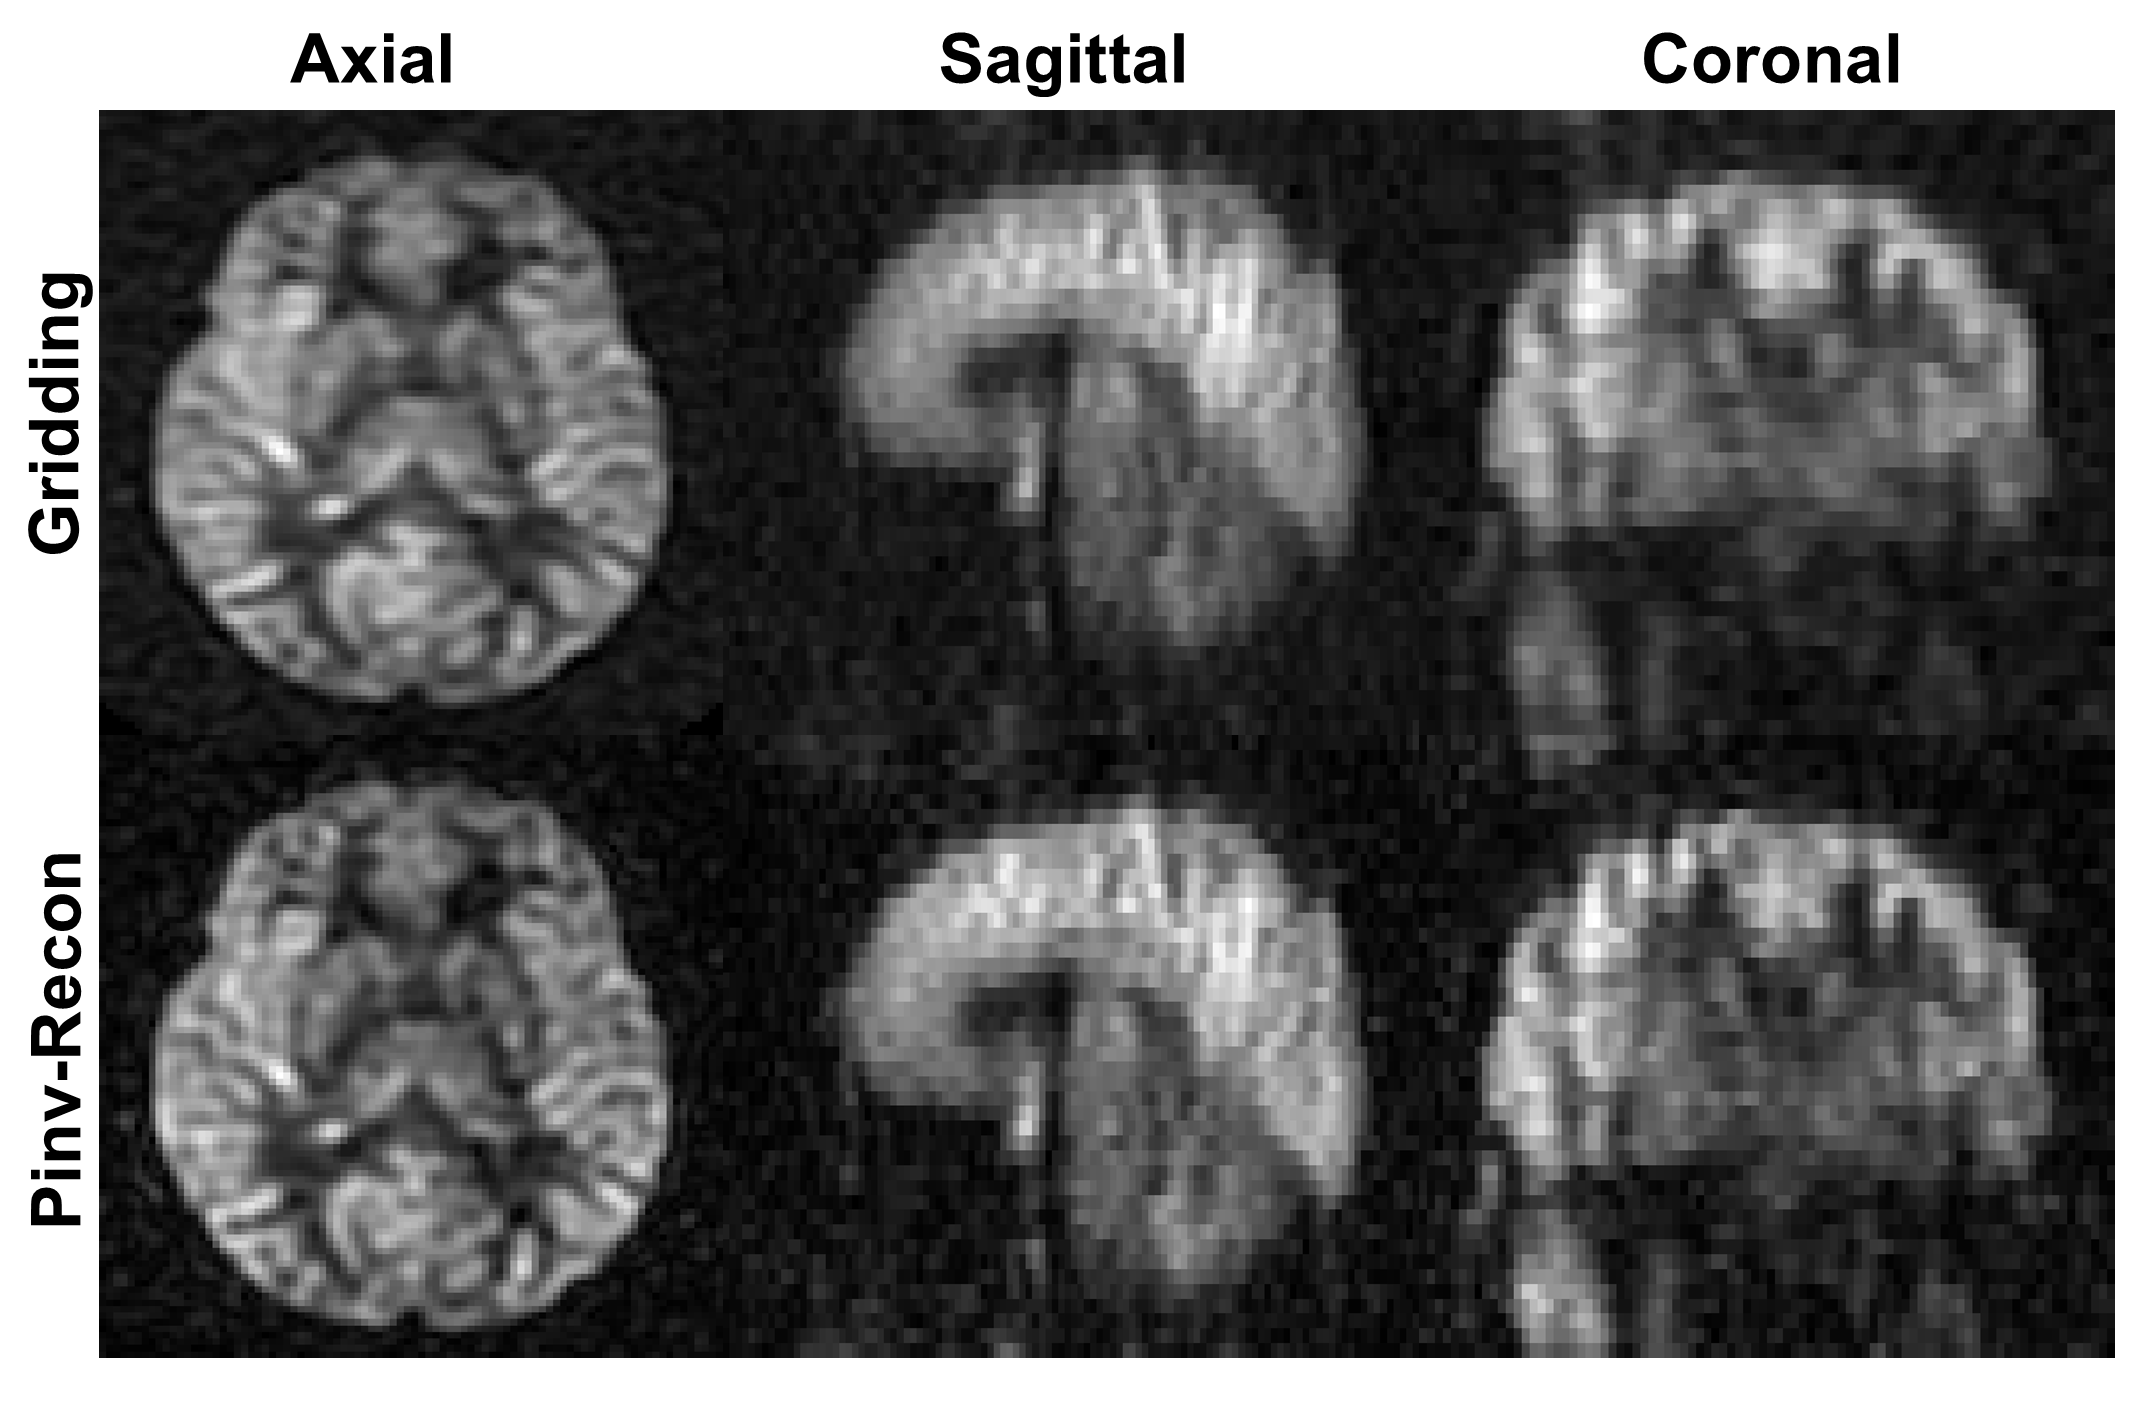

Separable 3D Pinv-Recon was demonstrated using a high-resolution abdominal 3D stack-of-stars spoiled gradient echo acquisition (Fig. 8) which has MTX 320 ×\times 320 ×\times 144. Similar to the ISMRM CG-SENSE reproducibility challenge, only image pixels in the masked region are included in reconstruction. The Z phase-encoding dimension was factored out via a 1D FFT, and the XY dimensions were reconstructed using Pinv-Recon, forming a 3D image which is shown in the leftmost column in axial, coronal and sagittal views.

The potential for real-time image reconstruction, i.e., updating the reconstructed image during scanning, is demonstrated in this dataset. Unlike gridding and iterative reconstruction methods, Pinv-Recon is data agnostic in that the reconstruction matrix can be calculated simply using the known trajectory, even before data is acquired. Once data acquisition finishes, only a simple matrix-vector reconstruction remains. The top row of Fig. 8 shows images obtained using increasing fractions of the available data spokes from left to right, indicating the potential for real-time updates during imaging. The acquisition time of certain MRI scans can last up to several minutes (6 minutes for this dataset), and real-time updates can be useful for radiographers or scanner operators to monitor the acquisition.

Comparison of Pinv-Recon and CGEncodeCG_{Encode} is shown in the bottom two rows of Fig. 8. The middle row shows images obtained using varying thresholds for Pinv-Recon with tSVD, demonstrating the trade-off between resolution and SNR offered by varying the condition number κ\kappa, also illustrated in the SVD spectrum on the right. The bottom row shows images reconstructed using CGEncodeCG_{Encode}. As is common with CG-based iterative methods, image quality first improves, peaks and then degrades with an increasing number of iterations.